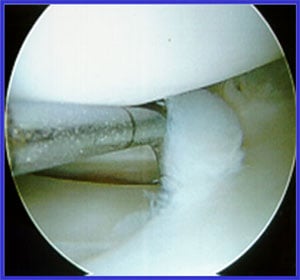

Arthroscopic photo showing meniscus tear.